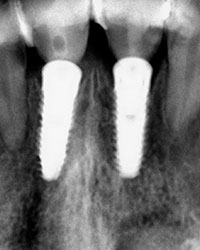

Decidimos: bajo anestesia local. previa asepsia y antisepsia, la limpieza de los alvéolos y la colocación de paralelos e implantes dentales.se colocan sus mismas coronas naturales para darle forma a los tejidos blandos y conservar papilas anatómicas.

Coronas Provisionales Inmediatas